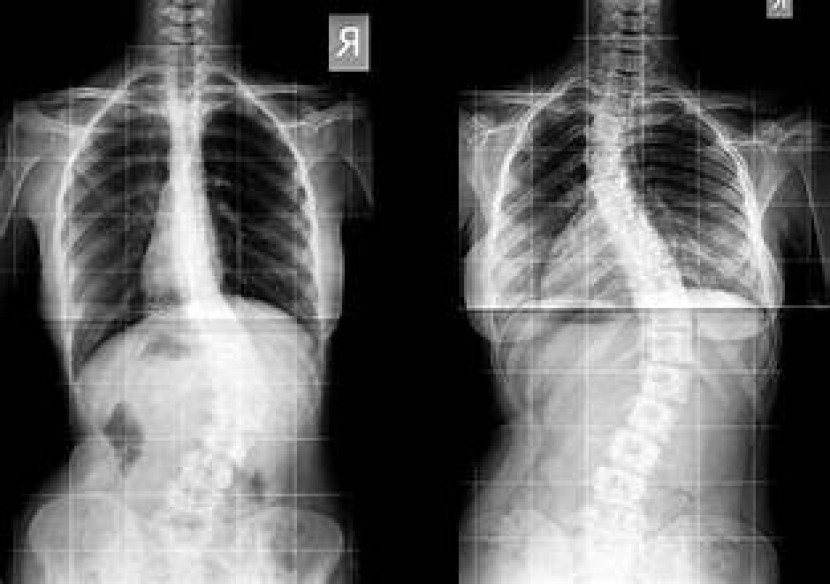

Sumber gambar : Celestial Blogging Hive

(website gambar: https://celestialblogginghive.blogspot.com/2023/05/macam-kelainan-tulang-belakang-yang.html)

Skoliosis merupakan dimana kondisi tulang mengalami melengkung atau menyamping, membentuk huruf 'C' atau 'S'. Kondisi tersebut biasanya sering terjadi pada anak remaja, meskipun penyebab pastinya terkadang tidak diketahui.